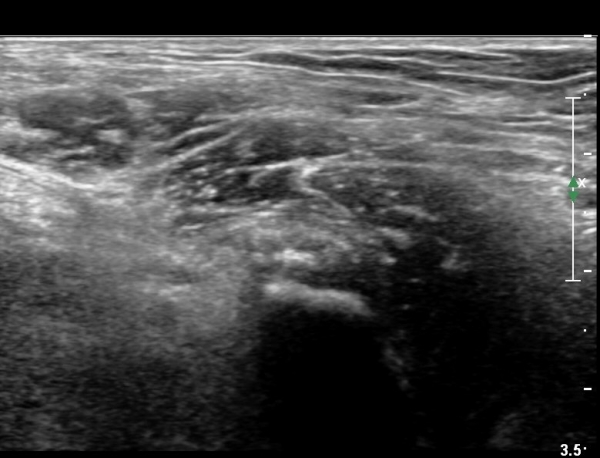

[¾ûµ¢ÀÌ] ÀüÇÏÀå°ñ±Ø °ß¿­°ñÀý(avulsion fracture of anterior inferior iliac spine)

Ç㸮¿Í ¾ûµ¢ÀÌ ÅëÁõ°ú ¿ìÃø ´Ù¸® ¶¯±è (±ÝÀÏ)

±ÝÀÏ ³Ñ¾îÁø ÈÄ ¸ñ, Ç㸮, ´Ù¸®ÀÇ ÅëÁõÀÌ ¹ß»ý. °ÉÀ» ¶§ ´Ù¸®°¡ ¾Èµé¸°´Ù.

´Éµ¿Àû SLR ¾ÈµÊ. ÀúÇ׿¡ ´ëÇÑ °í°üÀý ±¼°î°ú ¹«¸­ ½ÅÀü ½Ã ÅëÁõ°ú ±Ù¾àÁõÀ» º¸ÀÓ.